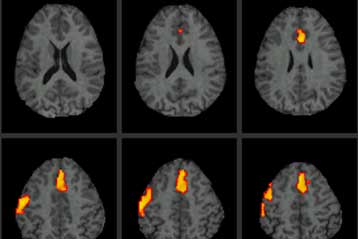

Λονδίνο: Ένα ενέσιμο υδροτζελ μπορεί να συμβάλλει στην ανάρρωση από την εγκεφαλική βλάβη, συντελώντας στην διέγερση της ιστολογικής ανάπτυξης στο σημείο του τραυματισμού, σύμφωνα με στοιχεία που φέρνει στο φως της δημοσιότητας το BBC.